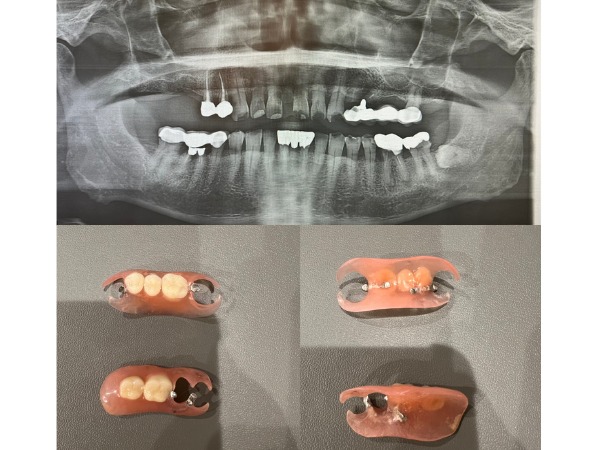

【症例】抜歯してから時間が経過し、被せ物と義歯で修復した治療

噛む力のバランスについて センター南デンタルクリニックでは、エックス線画像や口腔内写真から、患者様のお口の中で、『どういう状態なのか、なぜそうなったのか』原因を知っていただくために、歯型を取り、お口全体の話をさせていただいています。 私たちの食生活において、噛む力は大臼歯と呼ばれる奥歯によって支えられています。今回のように28本のうち1本を失っても、ご飯は食べられると考えている方は多いと思います。実際には、奥歯が噛む力全体の80%を支えているため、大臼歯を1本失うと、その分残った歯の負担が大きく増してしまいます。 噛む力のバランスが崩れてしまった場合に起きること 歯がすり減る 上下の歯は、就寝中の歯ぎしりで急速に歯を摩耗していきます。 知覚過敏が起こる 歯ブラシの毛先が触れたり、冷たいもの、甘いものなどの刺激によって、一過性の痛みが生じます。 歯の根元が欠ける 歯ぎしりや歯を横に動かしたときに上下の歯が強く当たることで歯にたわみが生じ、歯が細かく欠けてしまいます。 歯が割れてしまう 歯ぎしりや食いしばりによって、歯に非常に強い力がかかります。神経がある健康な歯でも割れてしまうことがあります。 歯の生える位置に影響を与える 噛みしめる癖があると、骨の発育が抑制されてしまいます。奥歯の高さが低く、前歯の噛み合わせが深くなったり、前歯の傾斜が強くなってしまったりします。成長期では、骨格の形成に影響を及ぼしてしまいます。 歯のまわりの組織が損傷する 日常生活での噛む力により、歯ぐき、歯を支える骨、顎関節が損傷することがあります。これは、歯並びや噛みあわせが深く関係しています。 修復物が破損してしまう むし歯をセラミックで修復した後、そこに負荷がかかってしまうと、割れたり欠けたりしてしまいます。 お口から全身に影響を及ぼすことがある 口が開かない、肩が張る、顎が痛い、舌が痛い、腰が痛いなど、全身に影響していきます。 噛む力のバランスが崩れてしまった場合(噛み合わせが悪い)、歯と歯の間に食べ物がはさまり、歯垢が溜まるため、虫歯と歯周病になるリスクが高く、結果として歯を失っていきます。 このようなリスクを防ぐためには、失った歯を放置せず、適切な治療で噛み合わせのバランスを回復することが大切です。 センター南デンタルクリニックでは、治療方法、使用する材質、治療費用についても、ご理解し、納得された上で治療をすすめてまいります。お気軽にお問い合わせください。 センター南デンタルクリニック 院長 吉竹絵里 こちらもご参照ください。 センター南デンタルクリニック|入れ歯治療 センター南デンタルクリニック|セラミック治療